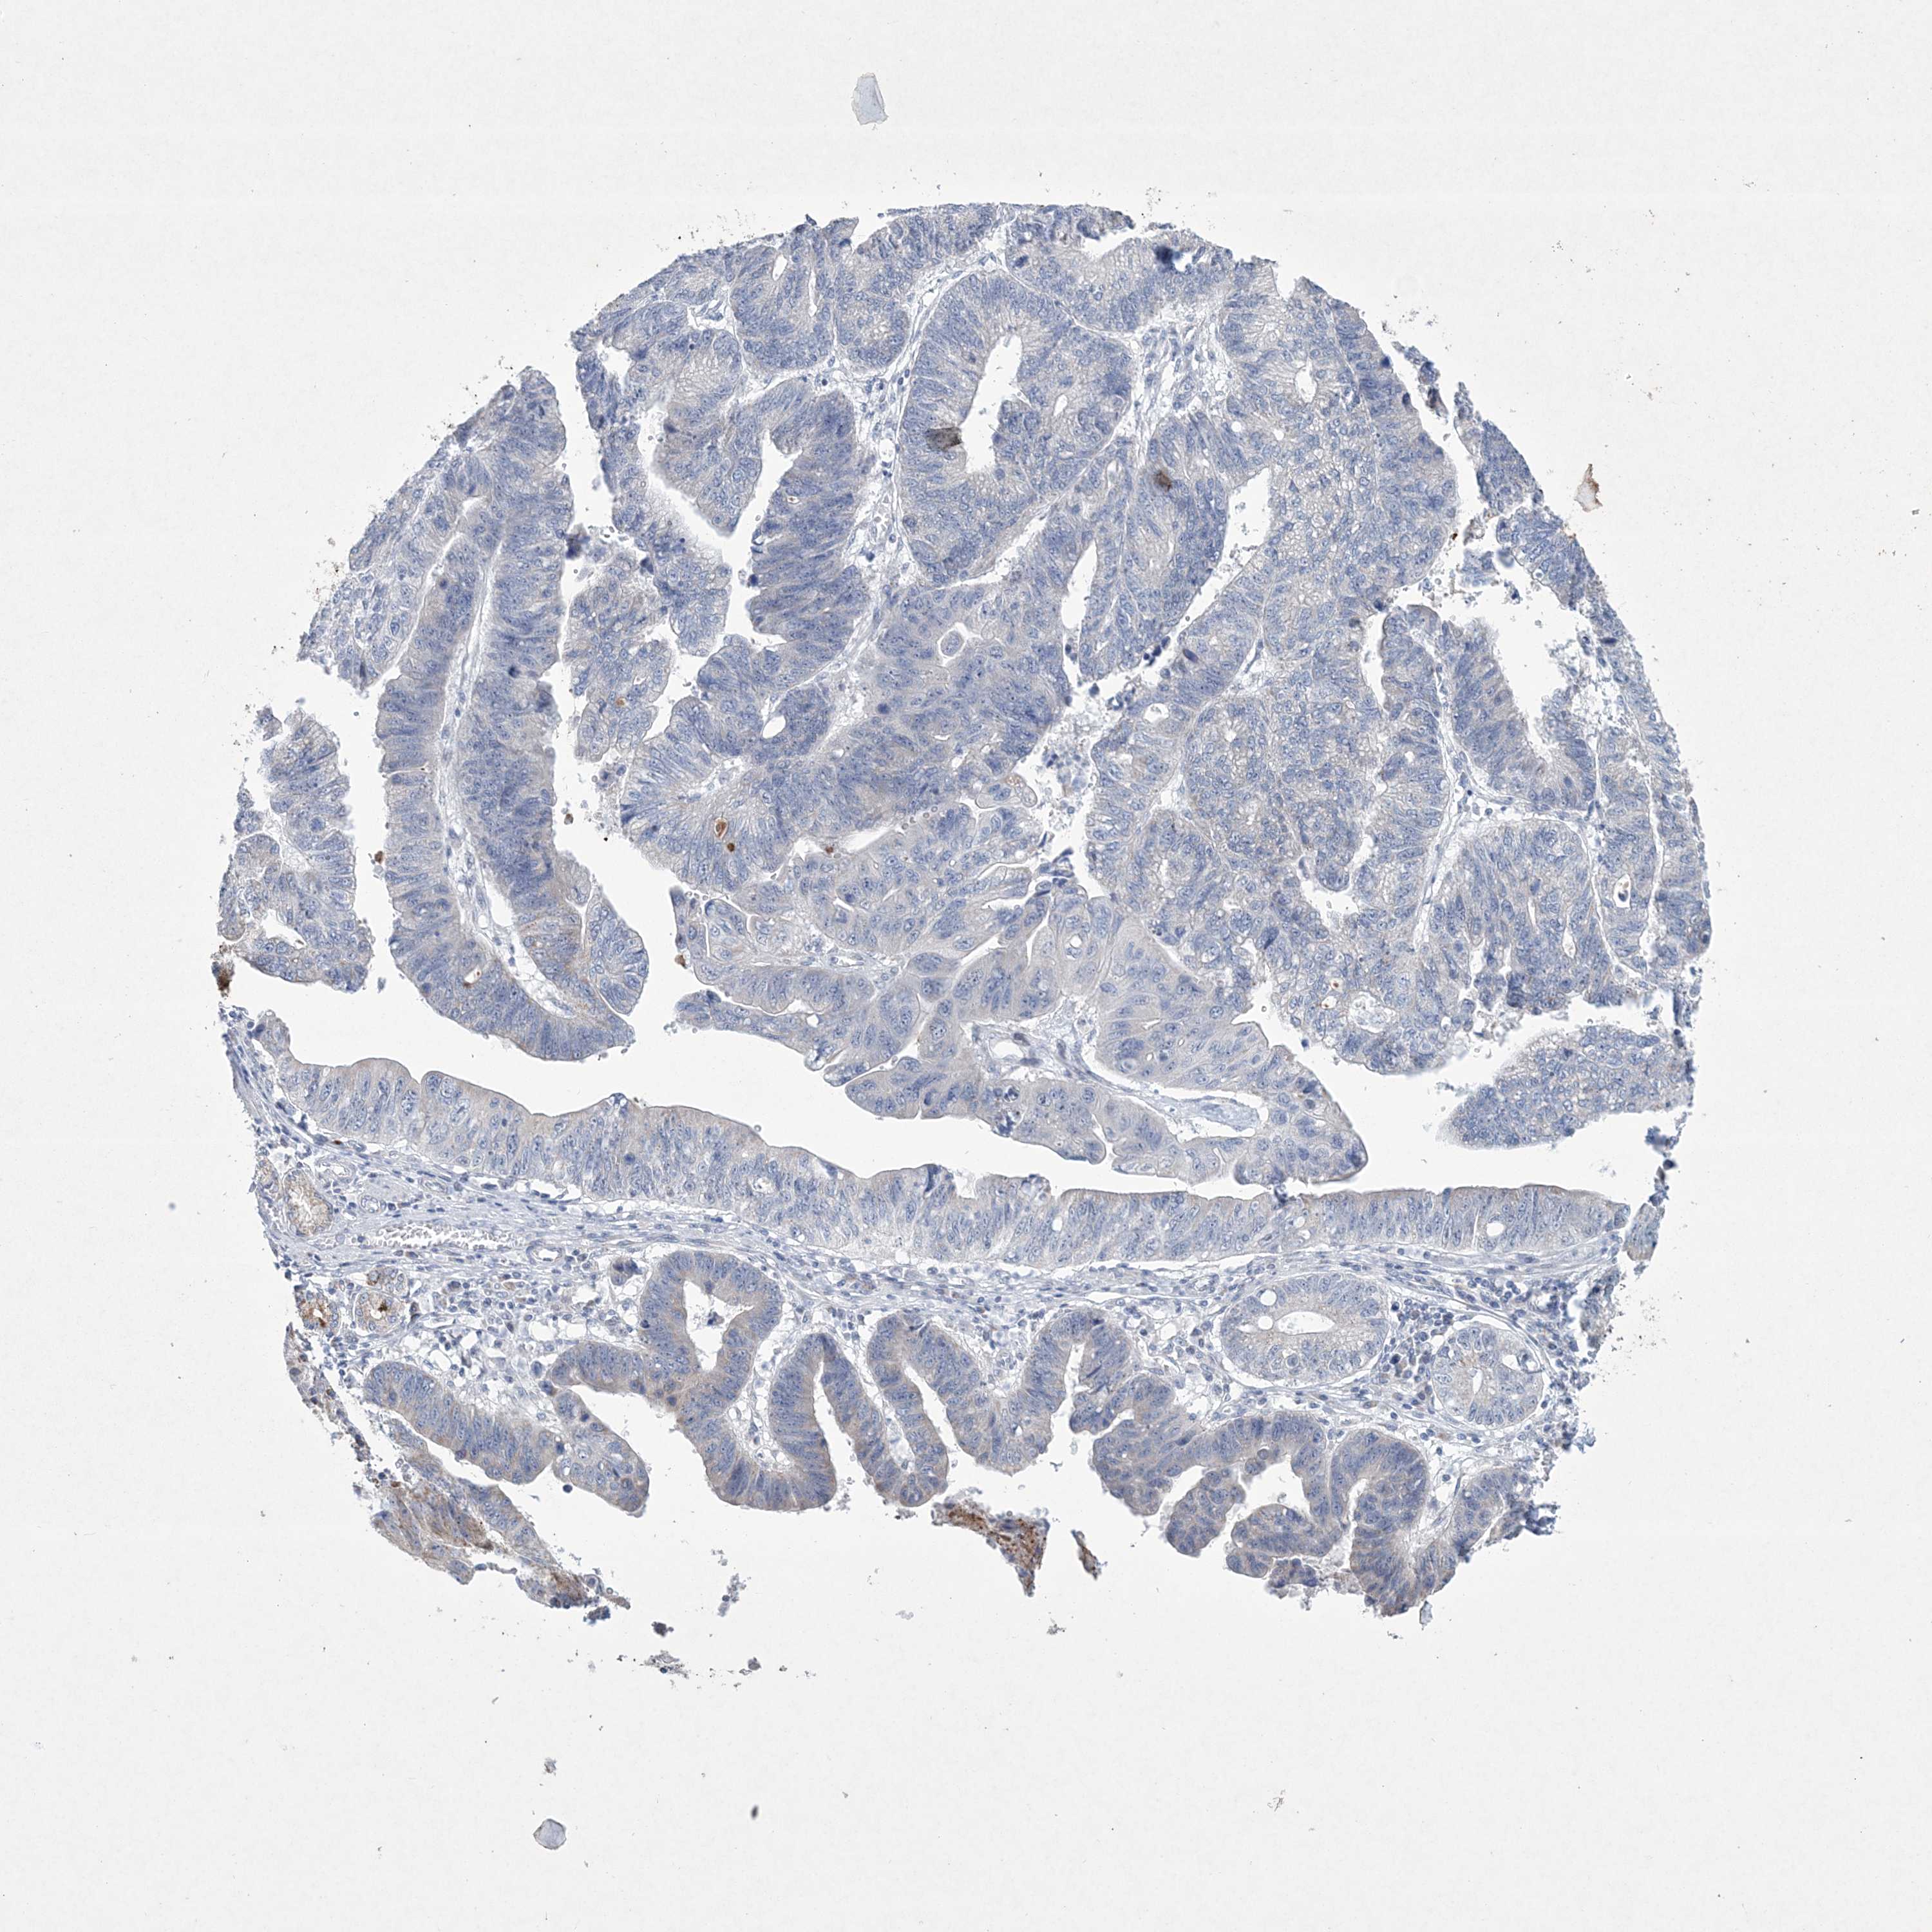

STOMACH CANCER - Protein expressioni

A mouse-over function shows sample information and annotation data. Click on an image to view it in a full screen mode. Samples can be filtered based on level of antibody staining by selecting one or several of the following categories: high, medium, low and not detected. The assay and annotation is described here.

Note that samples used for immunohistochemistry by the Human Protein Atlas do not correspond to samples in the TCGA dataset.

Antibody stainingi

Antibody staining in the annotated cell types in the current human tissue is reported as not detected, low, medium, or high, based on conventional immunohistochemistry profiling in selected tissues. This score is based on the combination of the staining intensity and fraction of stained cells.

Each image is clickable and will lead to virtual microscopy that enables deeper exploration of all samples and also displays staining intensity scores, fraction scores and subcellular localization as well as patient and tissue information for each sample.

Antibody HPA035701

Staining

High

Medium

Low

Not detected

Intensity

Strong

Moderate

Weak

Negative

Quantity

>75%

75%-25%

<25%

None

Location

Nuclear

Cytoplasmic/membranous

Cytoplasmic/membranous,nuclear

Adenocarcinoma, NOS